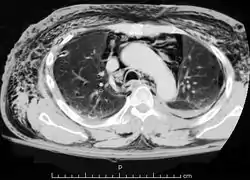

متلازمة هامان أو متلازمة ماكلين هي متلازمة من نفاخ تحت الجلد تلقائي[1] (هواء في انسجة الجلد)، واسترواح المنصف (هواء في المنصف، مركز التجويف الصدري)، ويرتبط أحيانا مع الألم.

| من أنواع | استرواح المنصف |